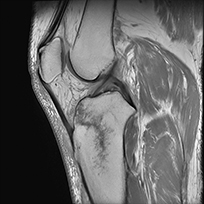

膝関節MRI T1強調画像

矢状断像

膝関節MRI